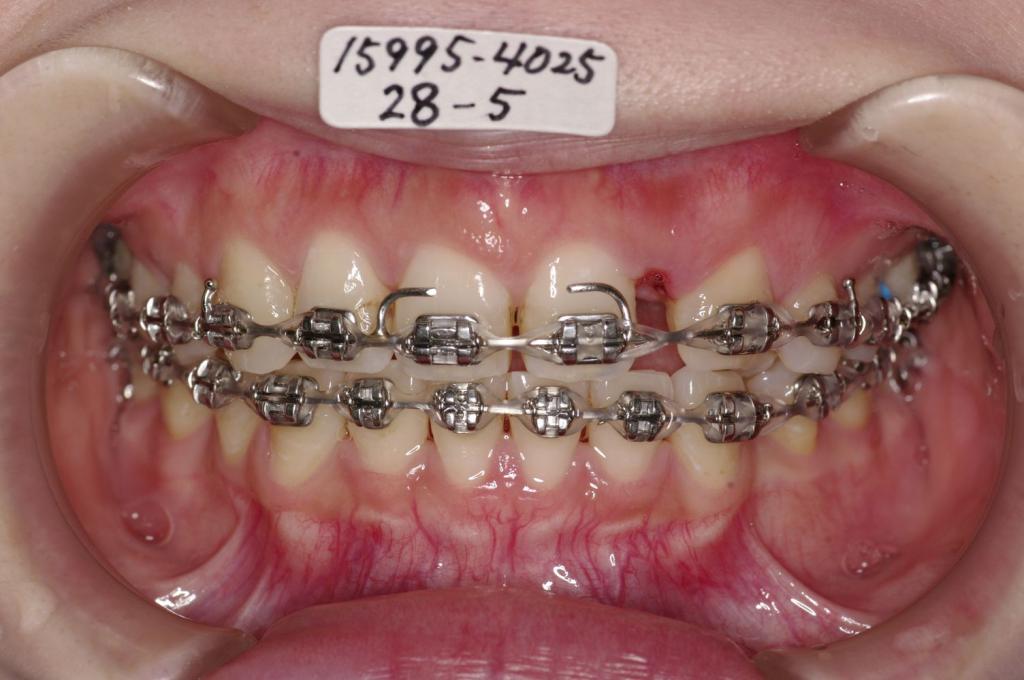

- 前歯、出っ歯・開咬の矯正治療

- 前歯の歯並び